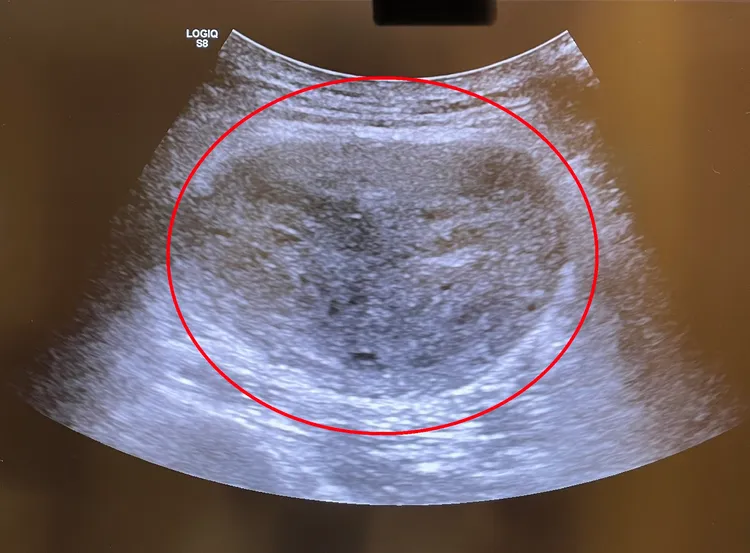

隔週病患回診時雖表示疼痛度降低,但再次超音波檢查時卻發現,腫瘤竟然「悄悄長大了」,大小已超過原先超音波線性(長條型)探頭,必須更換使用弧形探頭,且腫瘤成長速度可觀,幾乎大了快一倍;核磁共振影像報告也顯示,腫塊高度懷疑為惡性肉瘤,立刻安排轉介整形外科及放射腫瘤科評估處理,兩週後手術切除。

超音波影像檢視腫塊十分異常,建議進一步檢查及治療。院方提供

吳欣頤指出,第一次超音波檢查影像顯示,患者大腿半腱肌內有一小腫塊,大小約3-4公分,邊緣頗為規則,都卜勒超音波血流顯影異常,因此必須進一步掃描軟組織腫瘤,於是安排核磁共振檢查,並告知隔週務必回診確認影像結果。